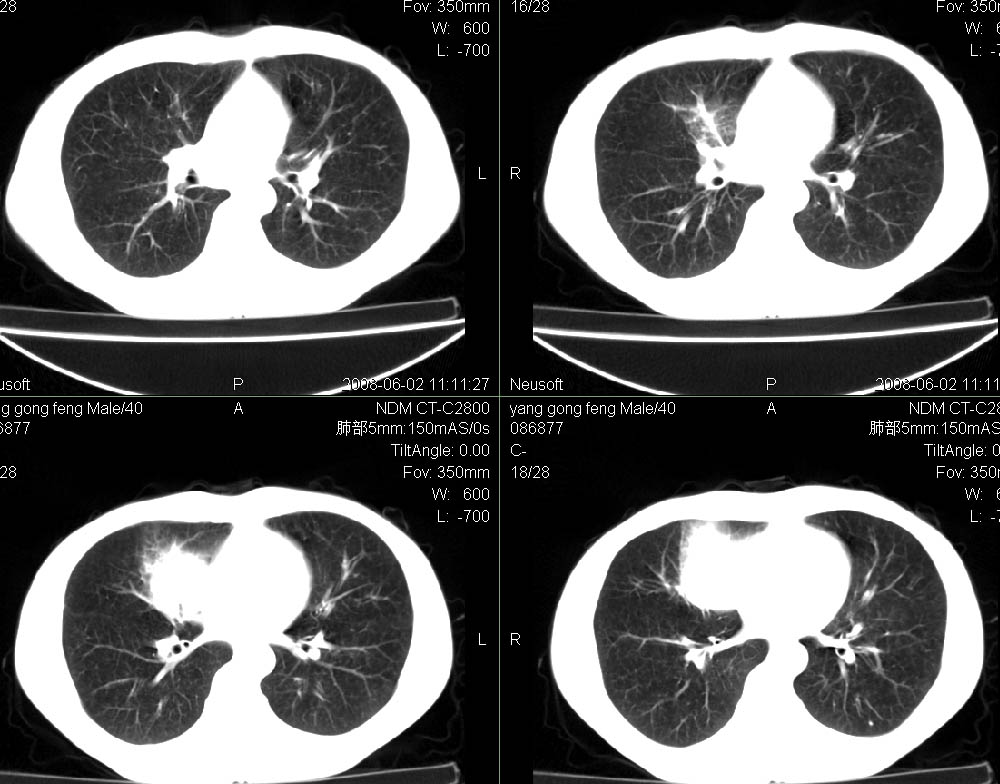

标题: CT15138:男,40,咳嗽胸痛. [打印本页]

标题: CT15138:男,40,咳嗽胸痛.

结合病史及临床表现考虑右侧中心型肺癌纵隔转移,

右侧中心型肺癌纵隔转移!

右肺中叶肺癌,纵隔淋巴结转移.

右侧中心型肺癌纵隔转移

考虑右肺中叶周围型肺癌并纵隔淋巴结转移。